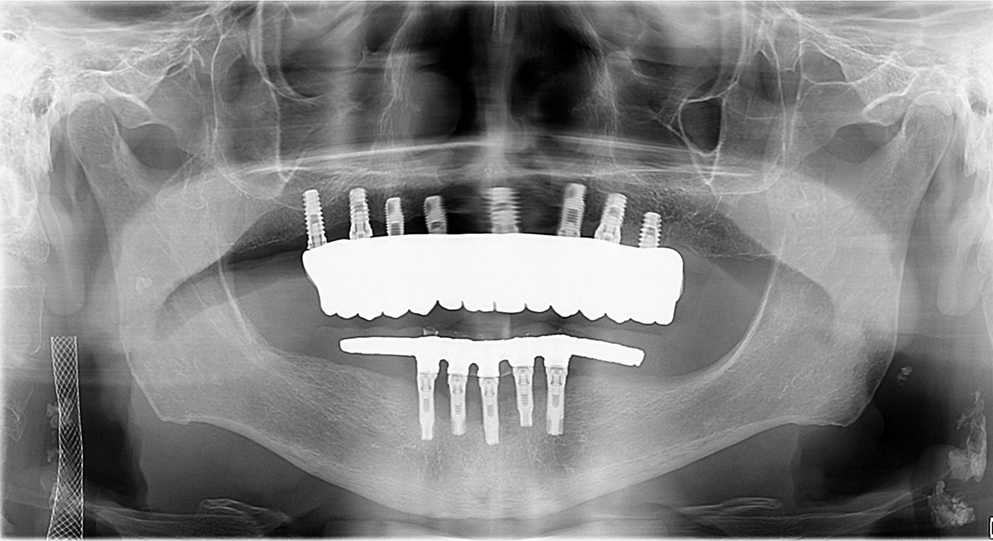

Na terceira consulta clínica foram instaladas as próteses monolíticas de zircônia. A adaptação da prótese foi confirmada com o teste de passividade dos parafusos e com a radiografia panorâmica.5,6 Um carbono articulado AccuFilm II (Parkell Inc, Edgewood, NY) foi usado para identificar contatos oclusais, e finas pontas diamantadas vermelhas foram usadas para ajustes oclusais sob água abundante. As próteses de zircônia foram entregues e os parafusos protéticos foram apertados com 10Ncm. Fita de teflon e resina composta Z250 (3M ESPE, St Paul, MN) foram utilizadas para selar os canais de acesso aos parafusos. O acompanhamento clínico e radiográfico de seis meses mostrou evolução estável (Figuras 9 e 10).